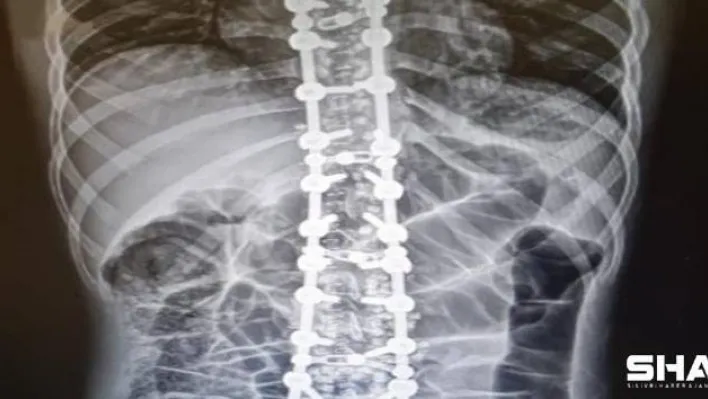

“En sık omurga problemlerinde kullanılıyor”

Osteopati vücudun her yerine uygulanabileceğini ancak en sık omurga problemlerinde kullanılmakta olduğunu ifade eden Özyurt, sözlerini şu şekilde sonlandırdı:“Omurganın patolojik olarak saydığımız faset eklem kitlenmesi, omurgayı dik durmasını sağlayan kasların spazmı ve diğer omurga problemlerinde güvenle kullanabileceğimiz yöntemler bulunmaktadır. Duruş bozuklukları, omurga ve kas- iskelet sistemi hareket fonksiyon bozuklukları, omurga disk kaymaları, kuyruk sokumu problemleri, eklem sertliği, migren, gerilim tipi baş ağrısı, uyku bozuklukları, iç organ kaynaklı kas-iskelet sitemi ağrıları gibi çeşitli ve birçok hastalıkta osteopati kullanılabilir. Osteopatinin tedavi süresi probleme, yaşa ve kişiye göre değişebilmektedir.”